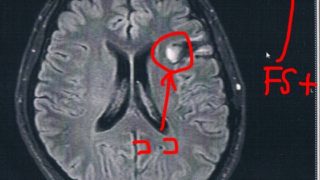

GLIOMA:悪性転化が無いかどうかの確認検査

前回10月の定期検査で腫瘍が大きくなってる↓かもしれないとの診断で検査時期を早めて、造影剤も注射してMRI検査をすることに。結果から言って、造影剤の入り込みも無く悪性転化は無いとのこと。言語検査に結果も特に問題無し。まあ、SLTA標準失語症...

GLIOMA:手術後51ヶ月目の検査

半年ごとの定期検査のために久しぶりに病院に戻った。2014/6/23の覚醒手術から約51か月になる。MRI検査の結果、半年前と比べても変化は無いように見えるが、一年前やそれ以前の画像と比べると若干変化があるようにも見える。と先生が言う。今回...